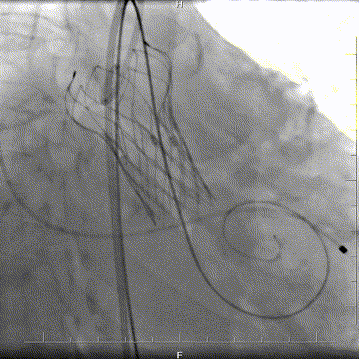

结合充分的术前讨论,和策略制定。术中团队建立双侧股动脉入路,以右股为主,使用18F球囊预扩张时未出现腰征,微量反流,因此选择植入24F瓣膜。由于LVOT呈喇叭型,心夹角偏大,最初选择-1mm释放,在释放过程中稍有位移,最终固定在0位,瓣膜充分展开,形态和位置都很好,术后跨瓣压差7-8mmHg,无反流,手术顺利完成。

球囊预扩